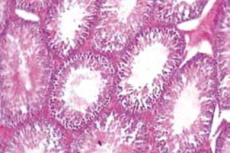

• Microscopic Standardization and Bioactive Profiling of Cissampelos pareira Roots